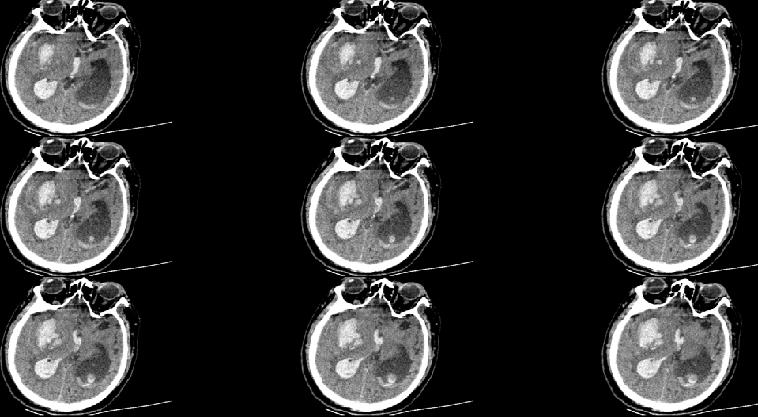

术后24小时CT